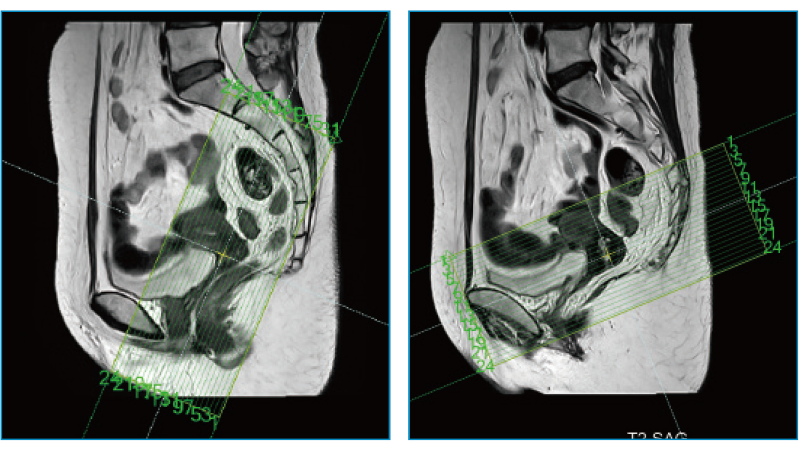

AutoPose FemalePelvis

スライスライン設定サポート機能"AutoPose"は、Scanogram撮像終了と同時にスライスラインを設定します。